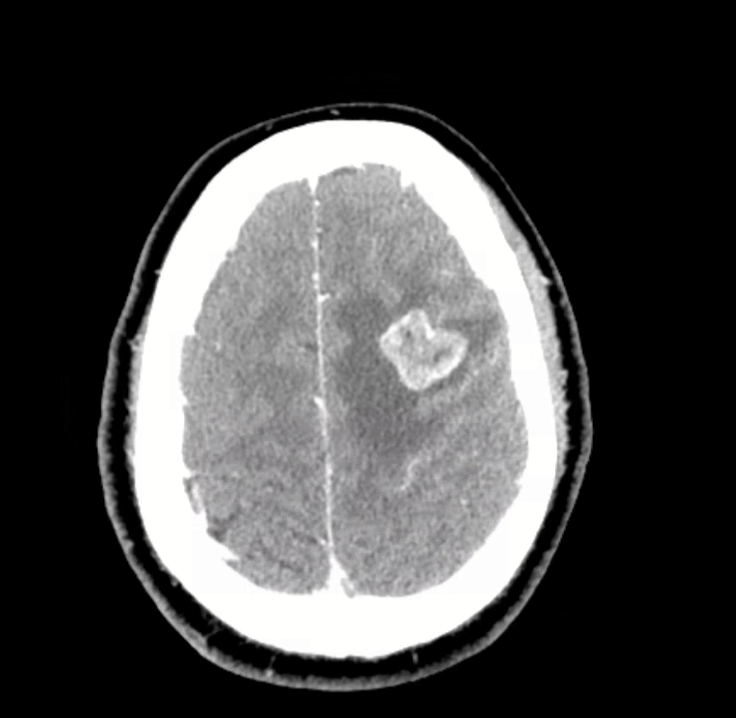

3) Neuro findings—ring-enhancing lesions

• Differential: septic emboli/abscess, nocardia, fungal, TB, parasites, metastases, vasculitis, sarcoid.

• Partner with neuroradiology for pattern nuances; treat seizures but keep searching for the unifying diagnosis.

• Path: TTF-1+, CK7+, napsin A → pulmonary adenocarcinoma with a fusion driver.

• Therapy: Targeted TKI (crizotinib) → dramatic radiographic response of miliary lung disease and CNS lesions.

• Teaching point: even “miliary TB-like” lungs + CNS lesions in a 20-something can be driver-positive lung cancer—don’t let age or pattern blind you.